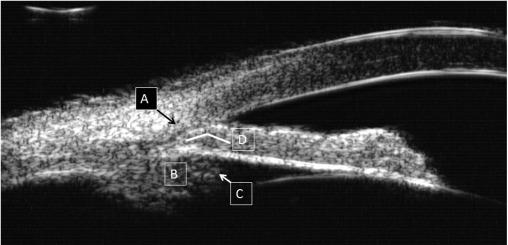

2- UBM

3- OCT segmento anterior

Qual utilidade da UBM no GPAF?

Diagnóstico diferencial do mecanismo de fechamento angular

Qual utilidade da OCT segmento anterior no GPAF? E qual sua limitação?

Diagnóstico diferencial do mecanismo de fechamento angular. além de medidas objetivas da câmara anterior e do ângulo

Limitado pois não avalia bem o corpo ciliar e outras estruturas posteriores à íris